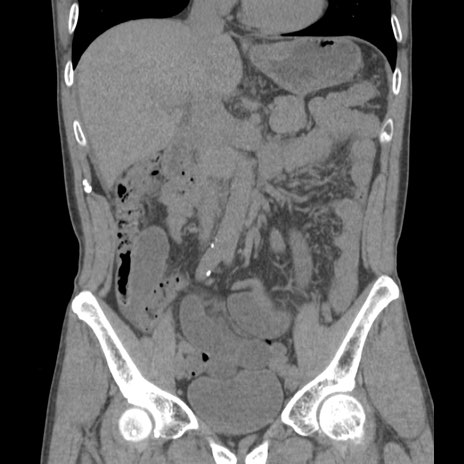

症例56 CT(冠状断像)

脂肪ウインドウ